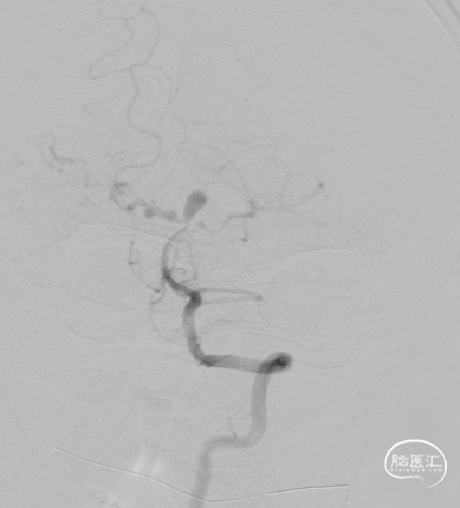

DSA:右侧P1段一6.8*9.7mm不规则囊状突起动脉瘤,远端P2段呈螺旋状蛇形动脉瘤改变。

DSA:右侧P1段一6.8*9.7mm不规则囊状突起动脉瘤,右侧A1段动脉瘤。夹层蛇形动脉瘤。

DSA:评估右侧后交通。

右侧颈内正位